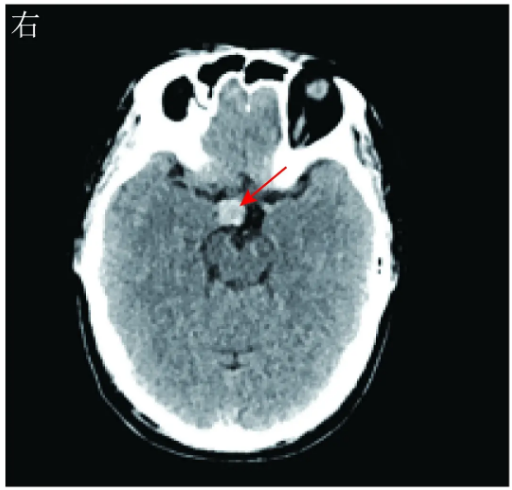

头颅MRI平扫示:鞍内垂体形态正常,鞍上区见不规则T1WI等信号、T2WI稍高信号影,大小约13 mm×17 mm(图2)。头颅增强MRI扫描示:鞍上区乏血供病灶,边缘清楚,结合MRI平扫结果考虑为鞍上区占位,表皮样囊肿可能(图3)。

图3术前头颅增强MRI扫描示,鞍上区乏血供病灶(红色箭头所示)。A冠状位B矢状位

胶样囊肿的CT影像学表现多为等密度影或稍高密度影,少数呈低密度影。典型胶样囊肿的MRI影像学表现为T1WI呈高信号,T2WI呈等信号或低信号,边界清晰,增强MRI扫描见囊壁强化,内容物不强化。由于胶样囊肿内容物的成分(黏多糖、胆固醇和较高浓度的顺磁性物质)复杂,故MRI的影像学表现多样。本例患者头颅MRI显示的T1WI呈等信号、T2WI呈稍高信号,不完全符合上述常见的信号特点,可能与囊腔内黏多糖含量高等因素有关。